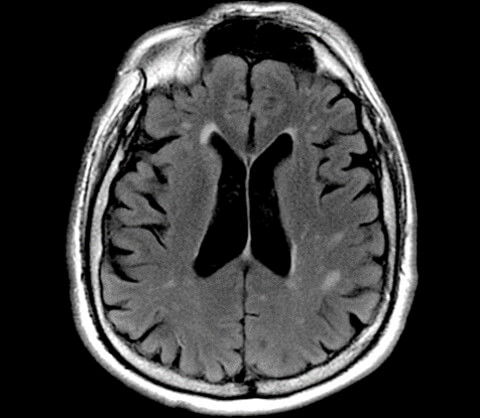

Here is an example of a FLAIR, a sequence used to suppress water or fluid. Before we talk about the sequence, we would like you not note the name. FLAIR, we know this is an inversion recovery because it has IR in the name. In the first two letters, FL tells us we are suppressing fluid.

Because there is so much fluid in and around the brain, this sequence is essential in brain imaging to look for things that may be hidden by that fluid. Note the bright lesions in the brain tissue, particularly in the parietal lobes. These are likely MS lesions or multiple sclerosis lesions. And these lesions may not have been visualized on a Spin echo or fast spin-echo. Flair is considered to be T2 weighted but notes the ventricles. On a regular T2, the ventricles would be bright because they are fluid and fluid appears bright. But we are suppressing fluid, so on this sequence, the ventricles are suppressed and appear dark. We use the appearance of the ventricles to determine that the inversion time is adequate.